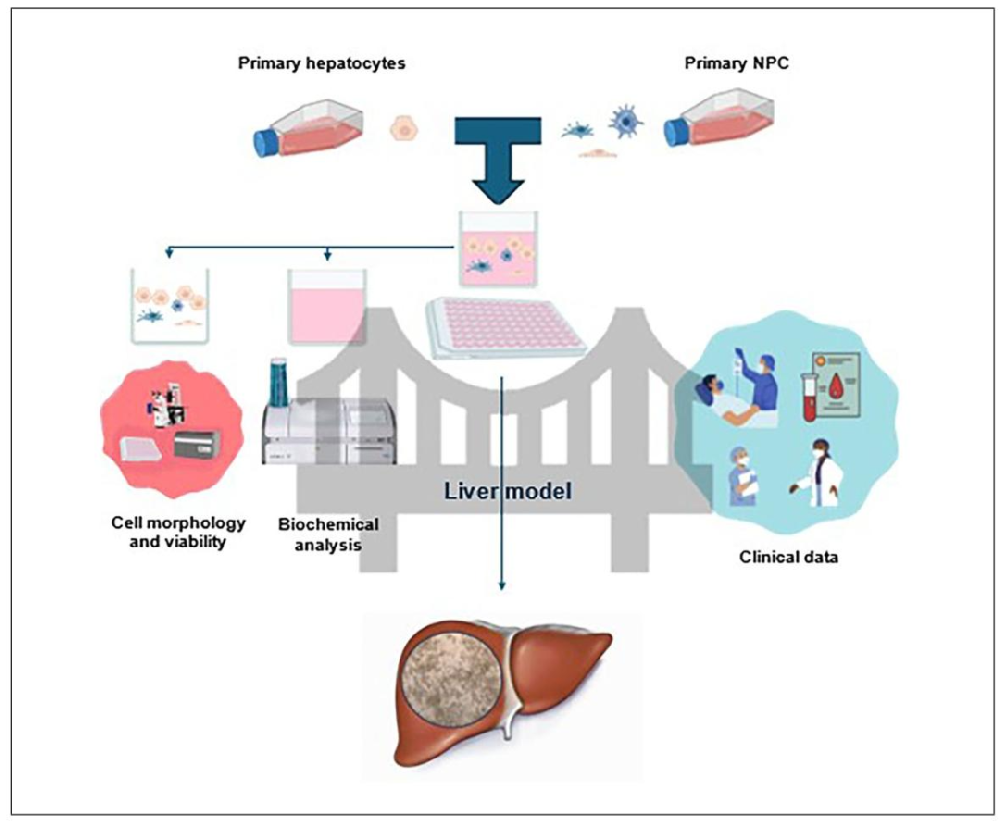

图 1:新型肝脏细胞培养系统实验流程

该图展示从细胞准备到功能分析的完整流程:1. 分别培养原代肝细胞与 NPCs(非实质细胞);2. 消化后按比例(肝细胞:NPCs=4:1)接种于 96 孔板共培养;3. 倒置显微镜观察细胞形态与自组装结构;4. 收集上清用 Cobas C111 检测生化指标;5. 采用 MPCVA 方法结合 ISX 评估细胞活力。流程设计核心是通过 “单独培养 - 共培养 - 双维度检测(形态 + 生化)”,确保模型的结构与功能一致性。